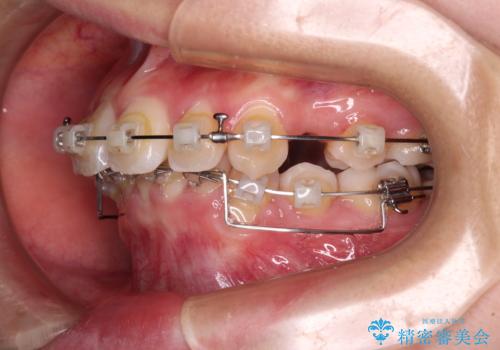

- クリアブラケット

- 前に傾斜して飛び出した上顎前歯を気にして来院された患者様です。

上下前歯の前後差が大きく、下顎前歯が隠れるほど深い咬合で、咬合力が強い状態でした。

口元の突出感を改善するために、上下左右の第一小臼歯4本を抜歯し、ワイヤー装置にて矯正治療を行うこととしました。

深い咬み合わせの改善に時間がかかりましたが、下顎前歯がしっかりと見えるまでに整えることができ、口元の突出感も大幅に改善することができました。